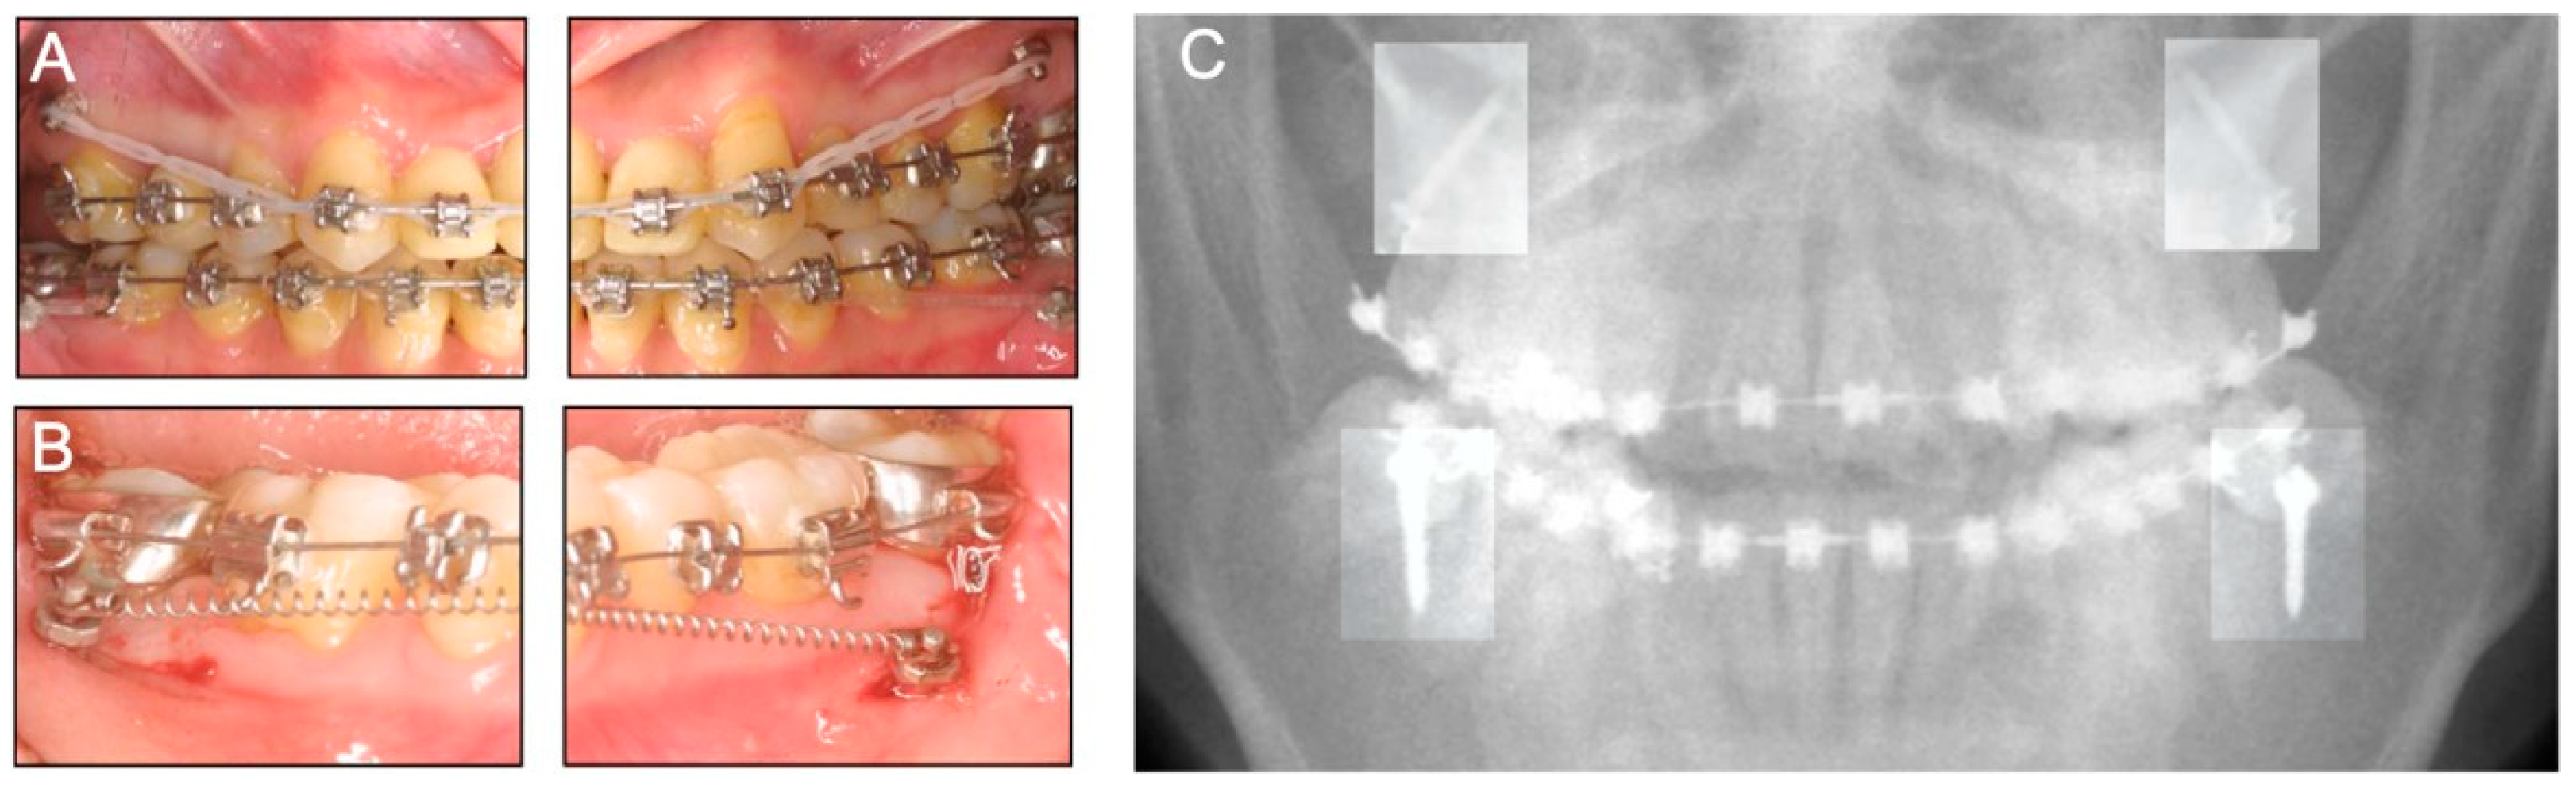

3. Case 2

3.1. Diagnosis and Etiology

3.4. Treatment Progress

3.5. Treatment Results